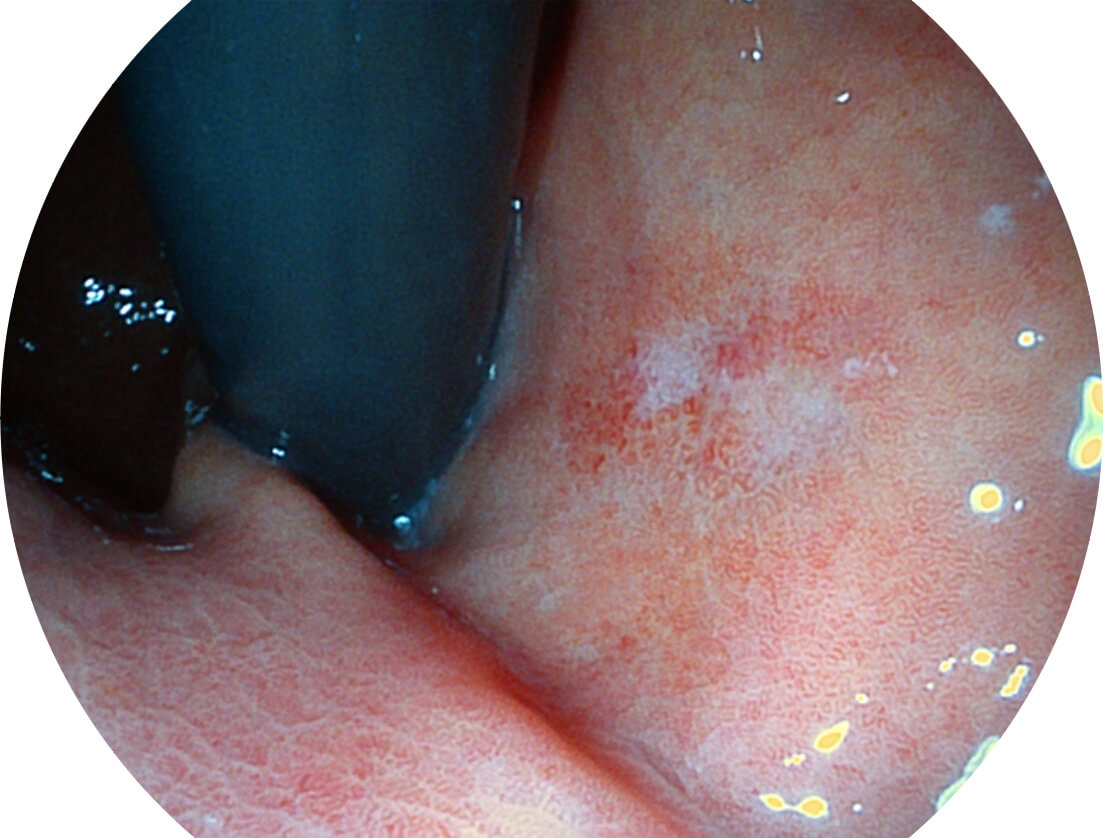

强调浅层黏膜结构的同时,保证照明亮度和提升浅层微血管与中层血管颜色对比度,病变边界更清晰。

VIST图像